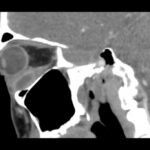

Soft tissue infections, including abscesses, are frequently encountered in the emergency department. However, abscesses of the inferior rectus muscle are rare and may present unique diagnostic and therapeutic challenges due to the scarcity of documented cases. This case report highlights the treatment of a 47-year-old male presenting with an abscess in the left inferior rectus muscle due to an acute Methicillin-resistant Staphylococcus aureus infection. Imaging revealed a distinct fluid collection compressing the left globe, causing restricted ocular motility and other symptoms. Despite prior intravenous antibiotics, the abscess persisted. While intravenous antibiotics are an important component of treatment, this case highlights the potential insufficiency of this approach alone, emphasizing a need for surgical intervention such as orbitotomy for drainage. This report contributes to the limited literature on inferior rectus muscle abscesses and underscores the need for further research and clinical attention to optimize patient outcomes.